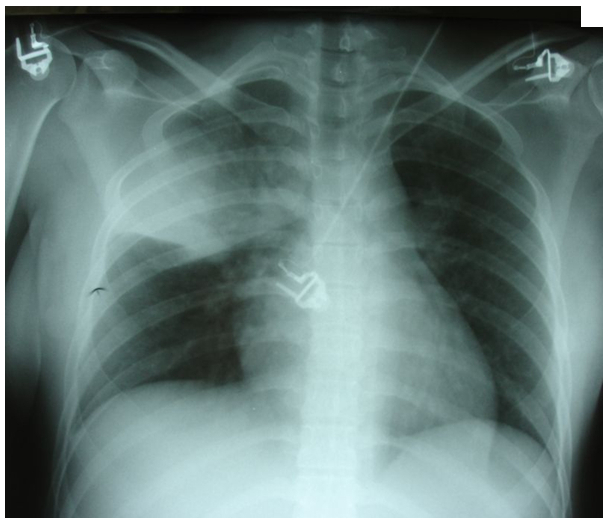

La patiente vous dit que depuis quelques jours elle est enrhumée et que depuis 24 heures elle se sent très fatiguée, essoufflée à l’effort et qu’elle tousse beaucoup. À l’entrée, la patiente a du mal à répondre aux questions. Elle est fébrile à 39 °C. Sa fréquence respiratoire (FR) est à 30/min et la fréquence cardiaque (FC) à 125 bpm. L’auscultation révèle des râles sibilants diffus et des râles crépitants apicaux droits. Le débit expiratoire de pointe est à 43 % de la théorique. La saturation artérielle en oxygène (SpO2) est à 88 %. La radiographie est la suivante. Figure 1.

Question 2 - Comment interpréter la radiographie (une ou plusieurs réponses exactes) ?

Le lobe supérieur droit est ici touché. Deux descriptions de sémiologie radiologique sont possibles. La partie médiale correspond à une image alvéolaire : elle est floue (nuageuse, cotonneuse), mal limitée, avec bronchogramme aérien (bronches toujours ventilées). La partie plus latérale est davantage condensée et renvoie à une atélectasie segmentaire. En effet, l’image est dense, opaque, sans bronchogramme aérien (bronches pleines) et rétractile (scissure attirée vers le haut).